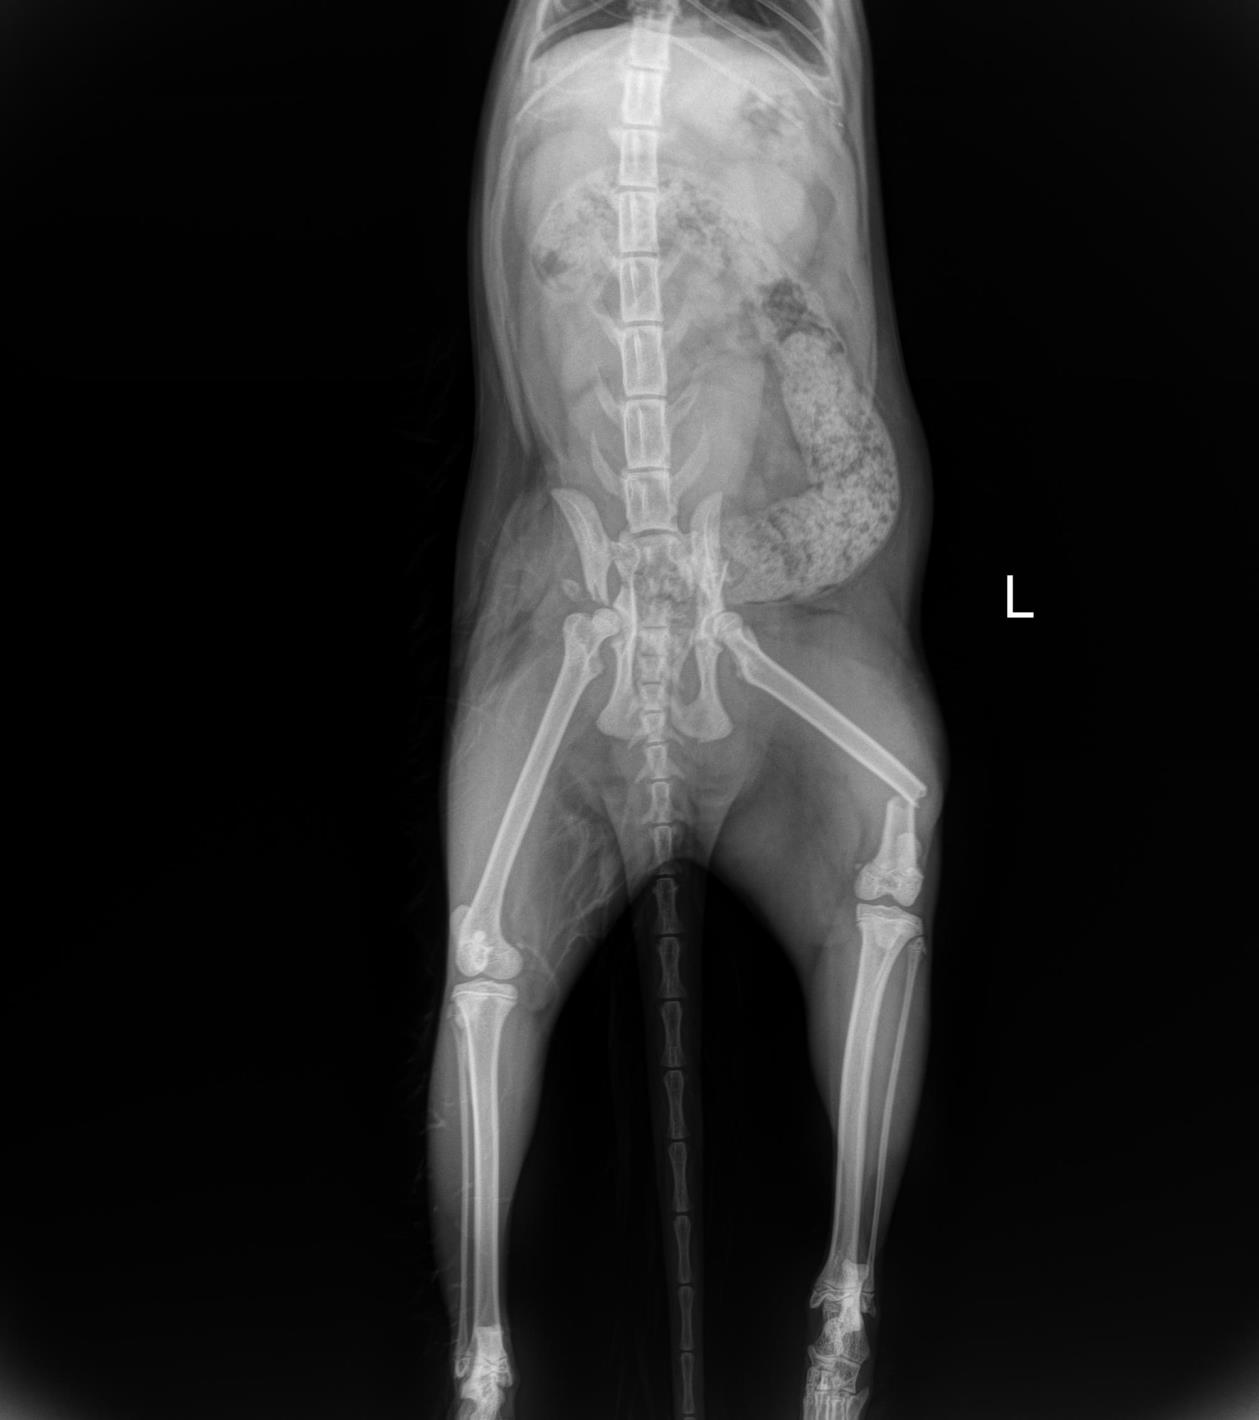

Our client Dr. Sonntag recently wrote us an email with the subject: Here’s why they changed the name of their cat to “LeiLOX”. With this email, he sent us a ton of x-rays - all of which were taken from a single cat patient.

Her owner traversed her with her car thinking it was a sack of flower soil. Sick at heart and believing her cat is going to die, but not giving up hope, the owner brought her to the animal clinic. (Spoiler alert: Dr. Sonntag bought a full LeiLOX kit 5 days before). Can you imagine what Dr. Sonntag was going to expect?

Day 1: He had to fix a humerus spiral fracture (left) with a LeiLOX bridge plate. Furthermore, he diagnosed a femur transverse fracture. Dr. Sonntag then used a 7-hole LeiLOX plate to repair this fracture, and do several emergency soft tissue surgeries.

Day 2: Repair of two iliac bone traverse fractures (left and right) with LeiLOX L-plates. Finally, several soft tissue surgeries were performed.